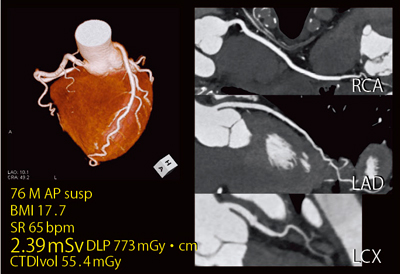

●症例3:狭心症疑い

76歳,男性,狭心症疑い例である。Flash Cardio Sequence(step and shoot法)で撮影した画像は末梢まできれいに描出され,実効線量は2.39mSvであった(図5)。

図5 症例3:狭心症疑い(Flash Cardio Sequence)